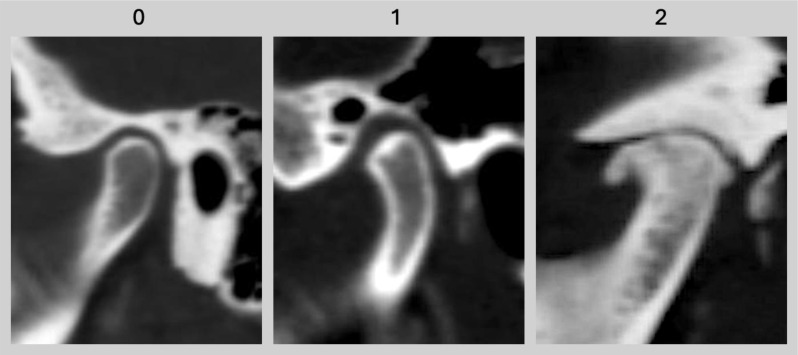

颞下颌盘双能计算机断层胶原蛋白密度成像。

Dual-energy computed tomography collagen density mapping of the temporomandibular disc.